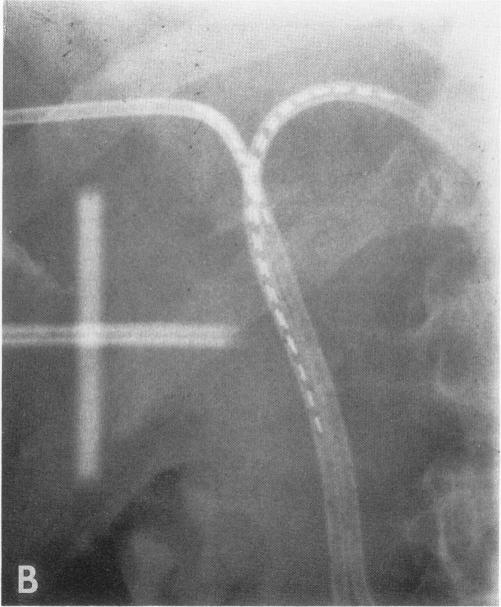

Thirty-four patients with subtotally resected or unresectable carcinoma of the extrahepatic bile ducts received radiation therapy; a minimum of 45 Gy (external beam) to the tumor and regional lymph nodes +/- 5-fluorouracil (5-FU). Seventeen patients received an external beam boost of 5 to 15 Gy to the tumor, and a specialized boost was used in the remaining 17 patients (iridium-192 transcatheter seeds in 10 and intraoperative radiation therapy [IORT] with electrons in seven). The median time to death in all 34 patients was 12 months (range, 4 to 98-months). The only patients who survived longer than 18 months were those either with gross total or subtotal resection before external irradiation (2 of 6) or who received specialized boosts (192Ir, 3 of 10; IORT, 3 of 7). Local failure was documented in 9 of 17 patients who received external beam irradiation alone +/- 5-FU, 3 of 10 patients who received an 192Ir boost, and 2 of 6 patients who received an IORT boost with curative intent.